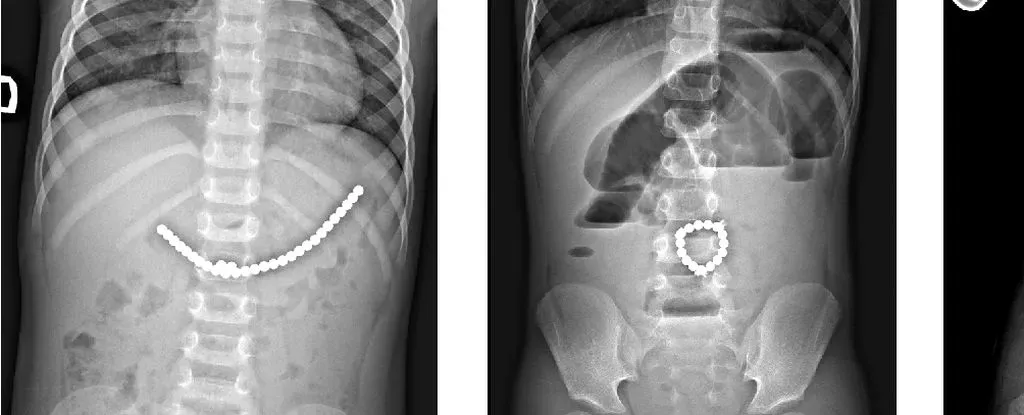

200 颗磁铁在患儿腹中形成了磁铁链。来源:Lekamalage et al.,?NZMJ, 2025

儿童吞食小型磁珠后的 X 光片。来源:Da?kevi?iūt? et al.,2017